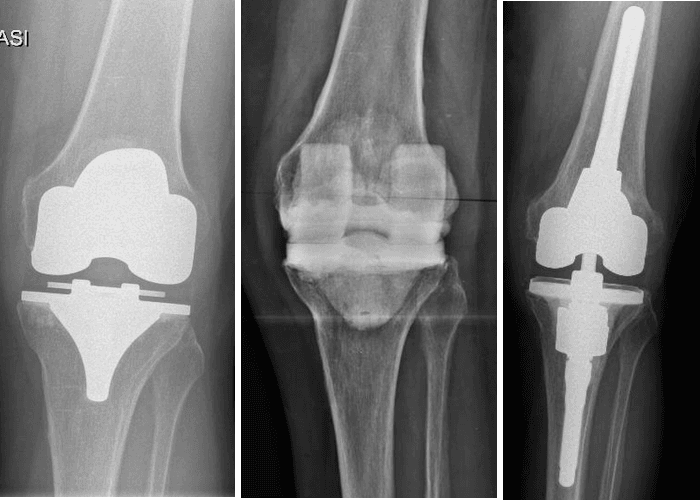

Una infezione può essere inoltre classificata sulla base del criterio temporale in acuta/precoce o ritardata/cronica. Si definisce una infezione acuta/precoce quando essa si verifica entro le 4 settimane dall’intervento di impianto protesico o dalla comparsa dei segni indicativi di infezione; in questo caso è possibile procedere con un intervento chirurgico chiamato DAIR (Debridement Antibiotic therapy Irrigation implant Retention). Oltre le 4 settimane dall’impianto protesico o dalla comparsa clinica di infezione ci troviamo di fronte ad una infezione ritardata o cronica/tardiva; in tal caso la scelta di trattamento ricadrà su un approccio chirurgico più invasivo di revisione protesica one-stage o two-stage. La scelta tra i due approcci verrà effettuata sulla base di molteplici criteri: microbiologici e clinici, relativi alla situazione infettiva attuale e alle caratteristiche generali del paziente, prendendo in considerazione diversi parametri, tra cui età, situazione dei tessuti molli, presenza di eventuali difetti ossei, condizione sistemica del paziente e comorbidità associate.

Il trattamento DAIR

L’intervento chirurgico di DAIR (Debridement Antibiotic therapy Irrigation implant Retention) consiste nella bonifica accurata dei tessuti, l’esecuzione di prelievi colturali intraoperatori, seguita dalla sostituzione delle componenti mobili (inserti, testina) con conservazione delle componenti protesiche osteointegrate/cementate, a cui si associa una terapia antibiotica mirata prolungata. Esso rappresenta una valida opzione nelle infezioni peri-protesiche precoci. Risulta tanto più efficace quanto più il tempo intercorso tra la comparsa dei sintomi e il trattamento chirurgico è breve, se è presente un isolamento microbiologico e se il germe risulta sensibile agli antibiotici.

La revisione two-stage

La revisione two stage rappresenta il gold standard per il trattamento delle infezioni periprotesiche croniche. Essa consiste nella rimozione delle componenti protesiche precedentemente impiantate, seguita da una accurata bonifica dei tessuti, prelievi intraoperatori per esami colturali e inserimento di uno spaziatore antibiotato, a cui verrà associata una terapia antibiotica mirata sulla base degli isolamenti microbiologici agli esami colturali. Costituisce l’opzione più valida e sicura nei casi di infezione peri-protesica difficile da trattare sia per motivi legati al germe patogeno resistente o difficile da isolare, sia per difficoltà dal punto di vista ricostruttivo a causa di importante perdita ossea e/o mio-cutanea. Il doppio tempo chirurgico rappresenta un’ottima soluzione per bonificare in maniera adeguata il sito infetto, consentendo al paziente di mantenere una buona qualità di vita, grazie allo spacer articolato che vicaria la funzione della protesi, e permettendo al chirurgo di pianificare in maniera ottimale il tempo del reimpianto.